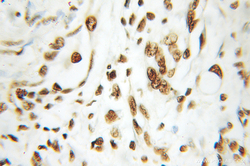

10197-1-AP IHC

Full details

Method: Other validation